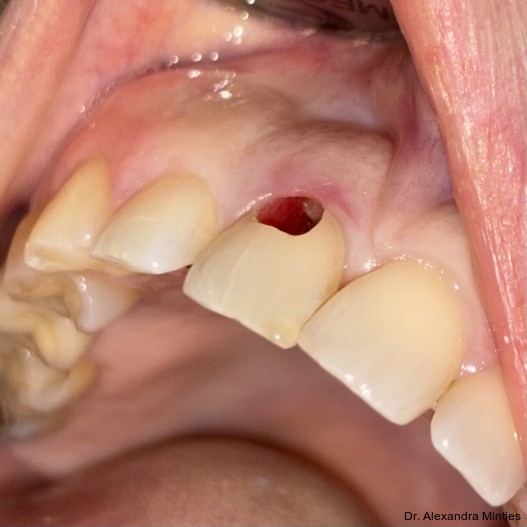

Entfernung der insuffizienten Restauration und Defektsanierung

Die Behandlung erfolgte in mehreren präzisen aufeinander abgestimmten Schritten. Zunächst wurde die alte Kompositfüllung vollständig und atraumatisch entfernt, ohne eine Blutung der Schleimhaut zu provozieren. Nur durch das minimalinvasive und vorsichtige Vorgehen bei der Entfernung der insuffizienten Kompositfüllung konnte die Blutungsfreiheit erreicht und somit eine solide Grundlage für die folgenden Behandlungsschritte gewährleistet werden. Anschließend wurde die weiche Zahnhartsubstanz mithilfe eines Rosenbohrers sorgfältig exkaviert (Abb. 3). Überschüssige Guttapercha wurde ebenfalls abgetragen, um eine saubere und stabile Basis zu schaffen.